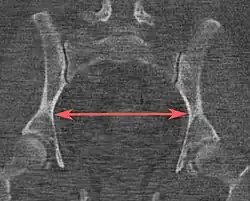

| Distância interespinhosa |

![]() Plano axial |

A linha entre os pontos ósseos mais próximos das espinhas isquiáticas | 9,5 a 11,5 cm.[6] | |